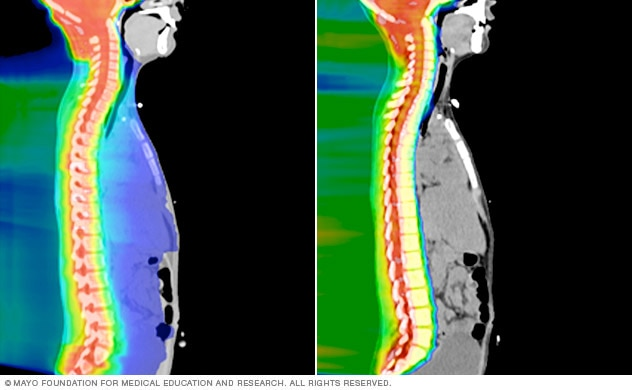

左侧图像:在传统的放射治疗中,x光(光子)传播到目标区域之外,以红色显示。蓝色突出了光子穿过身体时暴露在辐射下的区域。右图:在质子束治疗中,质子可以被编程为在深度停止,以消除对身体其他部分的不必要的辐射暴露。